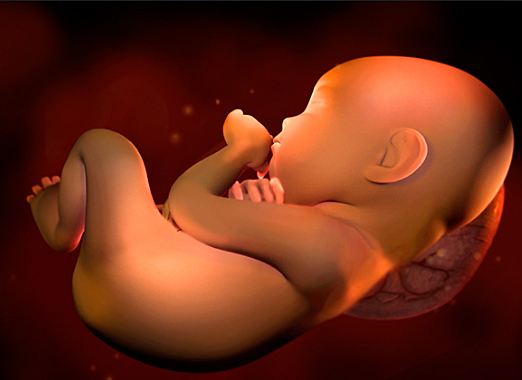

• Semana 30

Semana 30

El bebe ya pesa unos 1.350 gramos y mide unos 38 centímetros de la cabeza a los pies con 30 semanas de embarazo. Si todo transcurre con normalidad, la futura madre tendra que ir al ginecólogo hasta la semana 36 de embarazo, ya que las citas se dan cada cuatro o seis semanas.